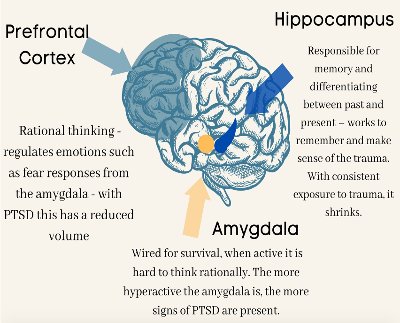

How Does Trauma Affect the Brain?

THE EMOTIONAL BRAIN, THE AMYGDALA AND PROCESSING EARLY WOUNDS

Difference Between the Amygdala and the Prefrontal Cortex

The Cortex and the Amygdala - SOAR Library - SOAR

PTSD, the Hippocampus, the Amygdala: How Trauma Changes the Brain